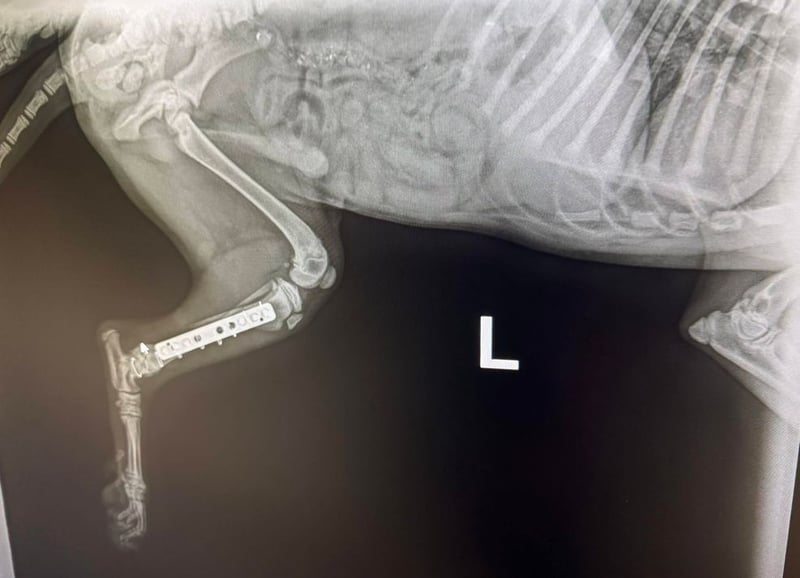

Bemerkungen: Hubsi wurde von einem Auto angefahren. Er hatte ein gebrochenes Hinterbenchen. Dieses wurde erfolgreich operiert.

Hubsi ist ein sehr lebhafter und verspielter Welpe und seit Mitte März 2026 in unserem Partnertierheim. Er kam zu diesem Zeitpunkt direkt aus der Tierklinik, denn er wurde in der Nähe einer Romasledlung von einem Auto angefahren und erlitt einen Bruch des Hinterbeinchens. Er wurde natürlich operiert und erholt sich momentan bei der Tierheimleitung im Wohnhaus.